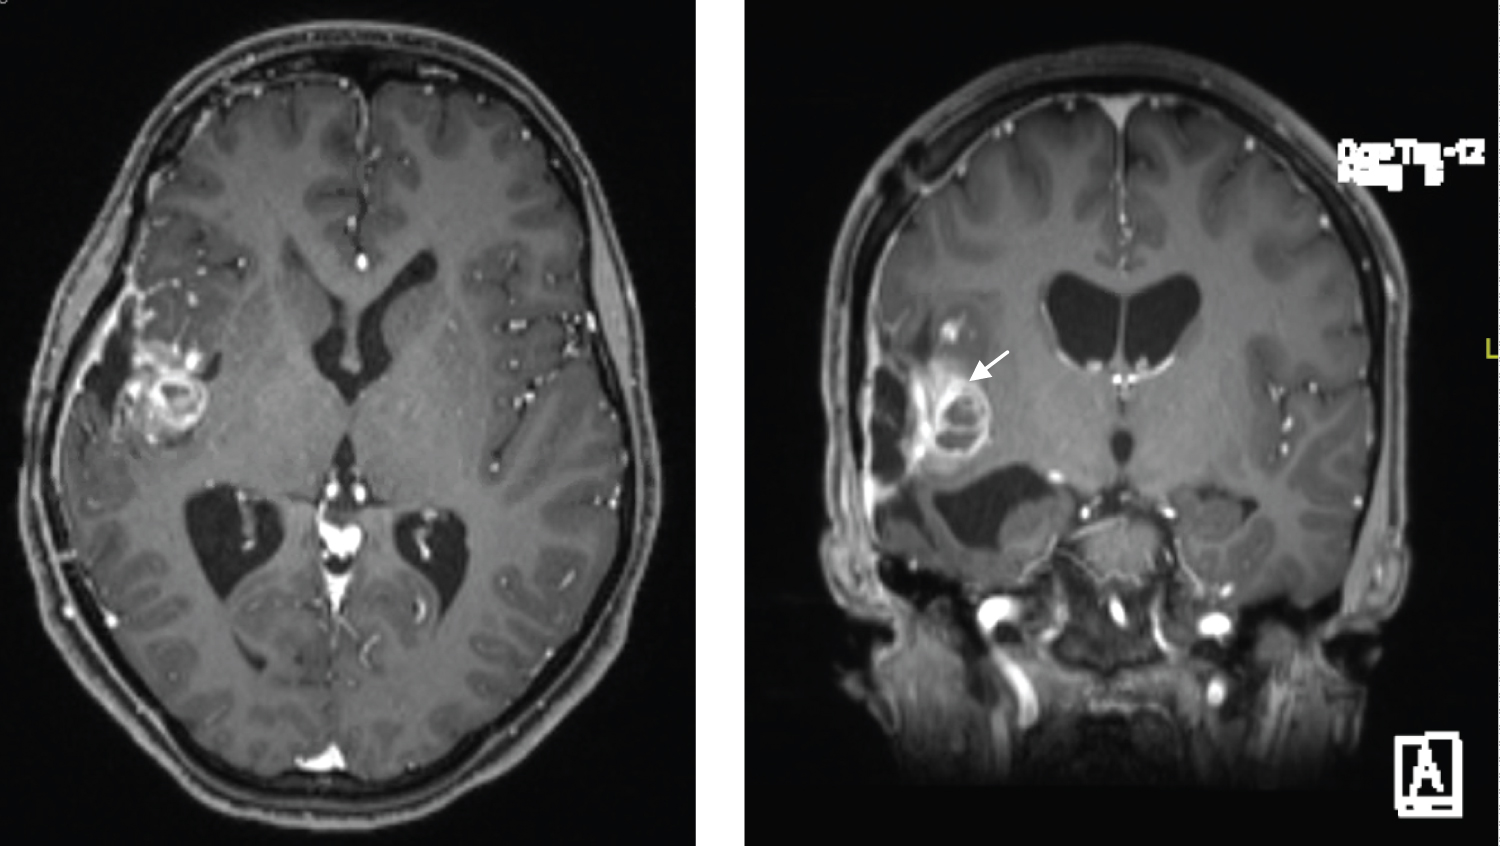

Before the surgical intervention, the patient underwent cerebral angiography (Figure 2). Moderate vascularity of the tumor was noticed, primarily through branches of the inferior division of the right MCA. There were multiple aneurysms within the tumor along with the inferior division of the right MCA.

Figure 2: Cerebral angiography (right ICA injections) AP and lateral views (A,B) prior to the surgical intervention, showing multiple small aneurysms along the inferior divisions of the MCA (Arrows). Post-embolization cerebral angiography lateral view (C) showing a significant decrease in vascularity "tumor blush" over the lateral aspect of the tumor (Arrow head). Obliteration of the aneurysms is shown (Arrows). View Figure 2

Embolization was performed through the inferior division of the right MCA; the procedure was uneventful. After embolization, vascularity was significantly reduced along the lateral aspect of the tumor with a residual supply along the medial portion of the tumor through the en passage vessels, which were not safe to embolize (Figure 2). Immediately after embolization, the patient was transferred to the operating room, where right frontotemporal craniotomy and tumor resection were performed. Intraoperatively, there was no dural thickening or a dural tail. The tumor was fibrous in nature but not vascular. The middle cerebral artery was coursing through its deeper component, which precluded gross total resection. Weighing the risk and benefits, we elected to leave some residual tumor.